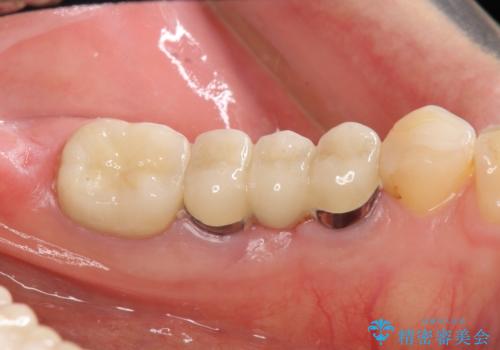

今回は破れにくいセラミック治療としてメタルボンドを選択しました。

外側からは金属色の見えない設計となっています。